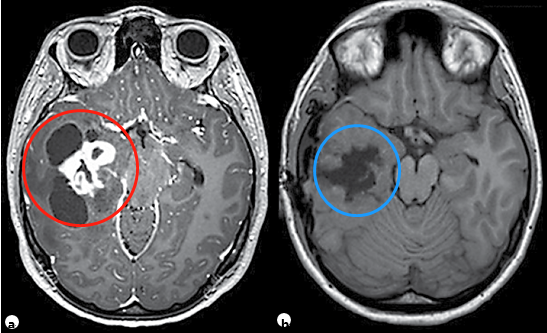

●神经节神经胶质瘤(WHO I级)是较常见的致癫痫性肿瘤,尽管它仅占全部脑肿瘤的1-4%。它往往发生在具有长期癫痫病史的儿童和年轻人中,通常难以凭借药物控制。复杂的部分发作较为常见。尽管神经节胶质瘤倾向于出现在颞叶,但它可发生在神经轴的任何地方,包括颈髓连接处、松果体和鞍上区域。颞部外的位置与组织学异型性和间变性相关(间变性神经节胶质瘤;手术是这些肿瘤的主要治疗手段[见图3])。虽然有报道称有恶性变可能,但其通常是良性的。幕上神经节胶质瘤通常可以手术全切,因此这是可治愈的,也为80%的患者达成了Engel I型发作结局。为了进一步好转癫痫发作的控制,建议行脑损伤切除联合邻近颞部新皮质切除术,肿瘤全切的主要障碍是肿瘤的中线位置(如脑干),而其他限制因素包括分界差、靠近主皮层和浸润了重要结构。

图3。11岁患儿,右颞部肿瘤多发囊肿并增强强化的实性瘤体部分,术前和术后轴位t1加权MRI对比,提示肿瘤被完全切除,病理诊断为神经节胶质瘤。